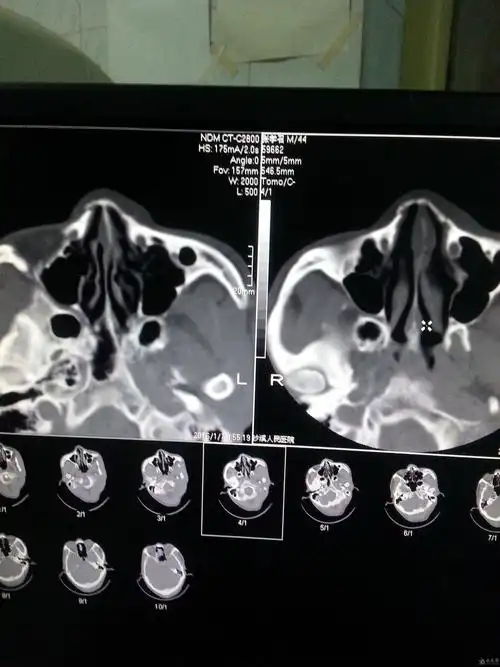

ct51740:鼻骨ct,请会诊!

双侧鼻骨,左侧眼眶内侧壁骨折 双侧筛窦浑浊鼻骨骨折

清晰图讲解鼻骨骨折影像学诊断